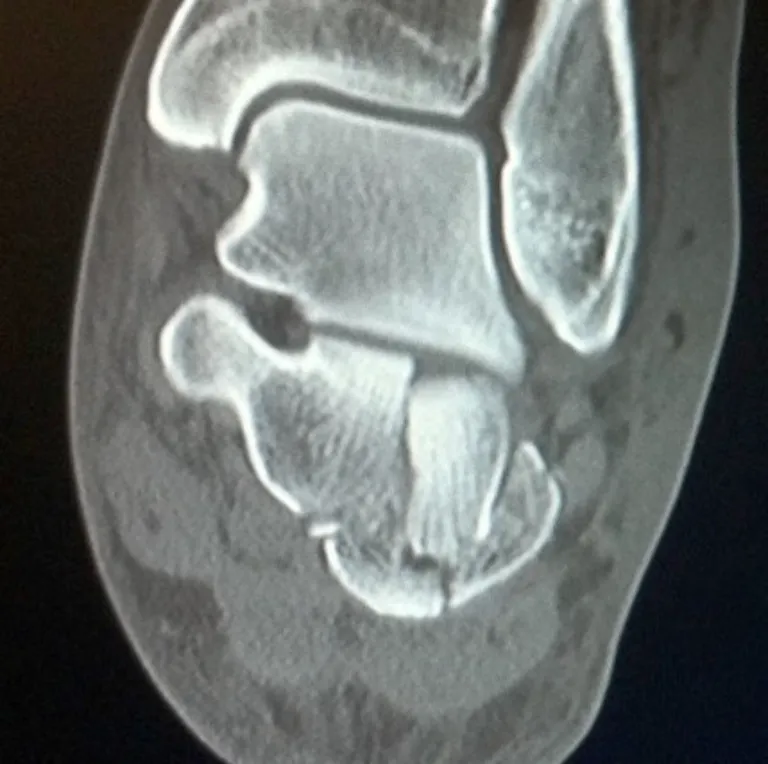

A CT scan is essential to accurately evaluate:

- The degree of articular involvement

- The number of fracture fragments

- Joint displacement

- Overall fracture morphology

The CT will identify the severity of the injury and whether surgery is indicated or not.

Severity is determined on the CT by:

- The degree of joint displacement

- Sanders classification on CT

Number of fragments and increasingly displaced. Greater disruption to the subtalar joint. Disruption of the calcaneocuboid joint.